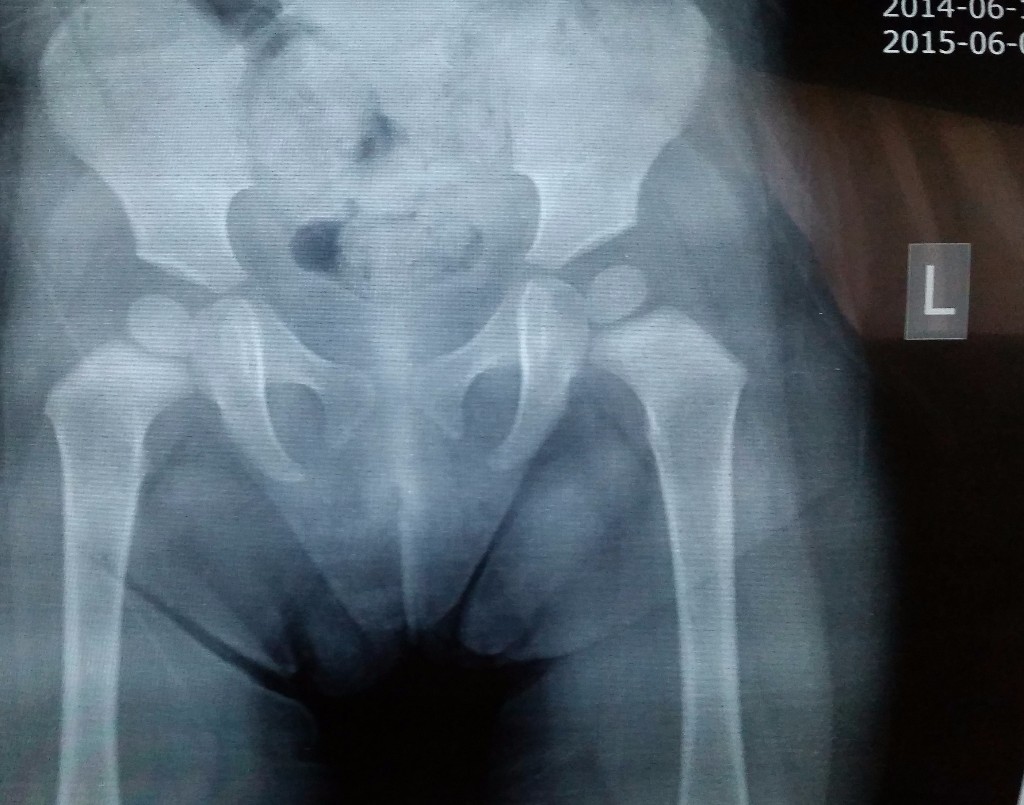

Рентген ТБС: Нормальные показатели